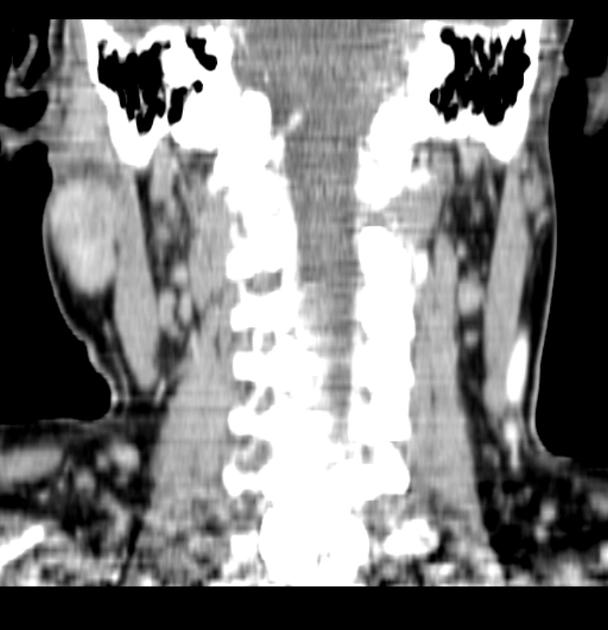

Sỏi tuyến nước bọt (Sialolithiasis)